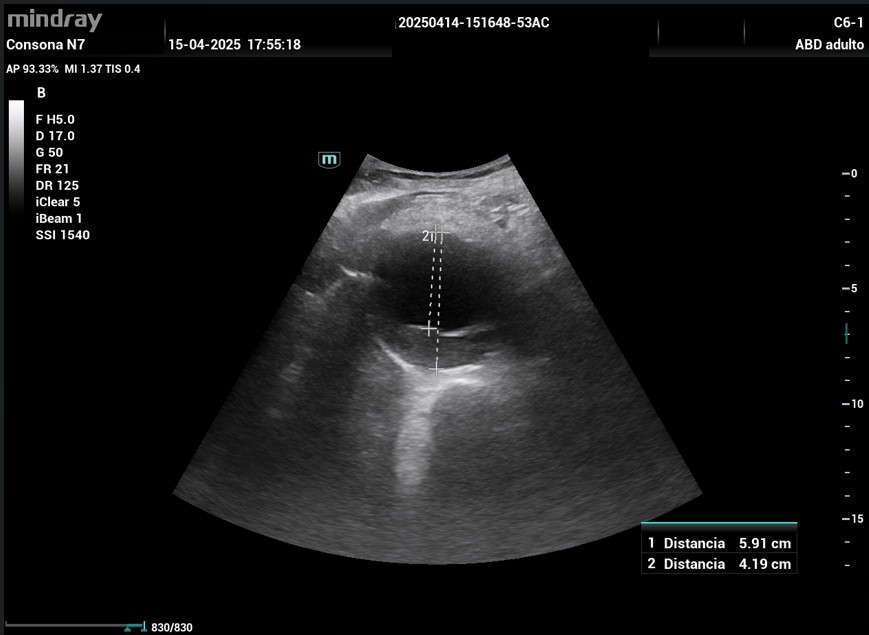

Ecografía en centro de salud: corte longitudinal paramedial izquierdo, se objetiva a nivel de epigastrio una dilatación lobulada de la arteria aorta abdominal (Imagen 1), que se inicia desde su porción suprarrenal y continua en todo su recorrido, afinándose al llegar a la bifurcación de arterias ilíacas.

En el plano transversal se objetiva la dilatación de la aorta de hasta 5,91 cm de diámetro total, con presencia de trombo mural en pared posterior que deja una luz respetada de un diámetro de 4,19 cm (Imagen 2). Con Doppler Color se visualiza el signo del Yin -Yang, que representa un flujo anterógrado y retrógrado que puede aparecer en aneurismas y pseudoaneurismas. (Imagen 3).